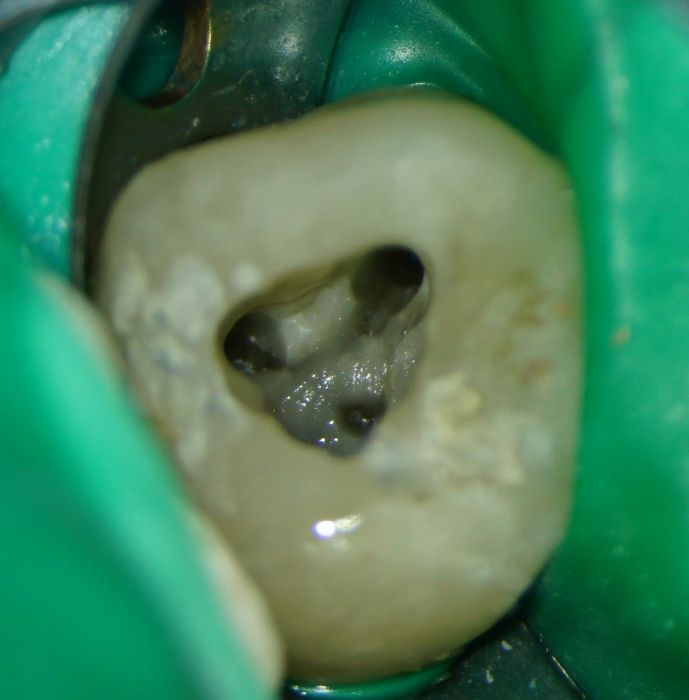

Ein Dental-Mikroskop ermöglicht bei Wurzelkanalbehandlungen bis tief in die Wurzelkanäle zu sehen. Dies ist einerseits durch die enorme Vergrößerung aber auch durch die perfekte Ausleuchtung möglich.

Über ein Mikroskop können z.B. kleinste Krümel und Gewebereste im Wurzelkanal erkannt werden, was die Behandlung viel kalkulierbarer und für den Zahn sicherer macht.

Hingegen sind bei der Schildertechnik die Form des Wurzelinstrumentes und die Guttapercha-Stifte kongruent bzw. formgleich. Bei der Aufbereitung unter dem Mikroskop bekommt der Zahnarzt mit speziellen Nickel-Titan-Instrumenten einen reproduzierbar konisch aufbereiteten Wurzelkanal. In diesen passen entsprechend konische Guttapercha-Sifte, die abdichtend ohne Zementspalträume eingefügt werden können.